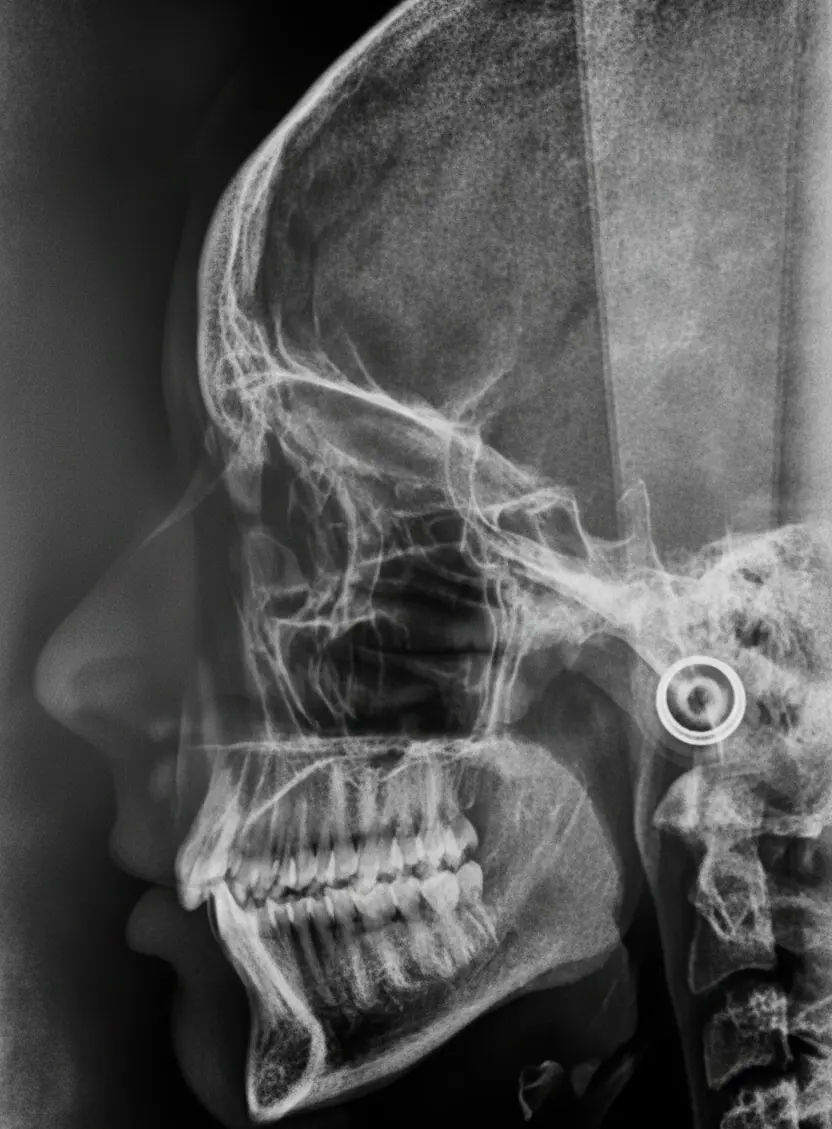

La cirugía maxilofacial es la especialidad médica que se encarga del diagnóstico, tratamiento y rehabilitación de todas las patologías y anomalías de la boca, la cara, los maxilares y el cuello. Es una disciplina integral, que va mucho más allá de la odontología tradicional, abarcando desde extracciones dentales complejas hasta cirugías reconstructivas y estéticas de la región facial.

Realizamos una valoración exhaustiva mediante exploración clínica y pruebas de imagen para diseñar el plan quirúrgico más seguro y eficaz.